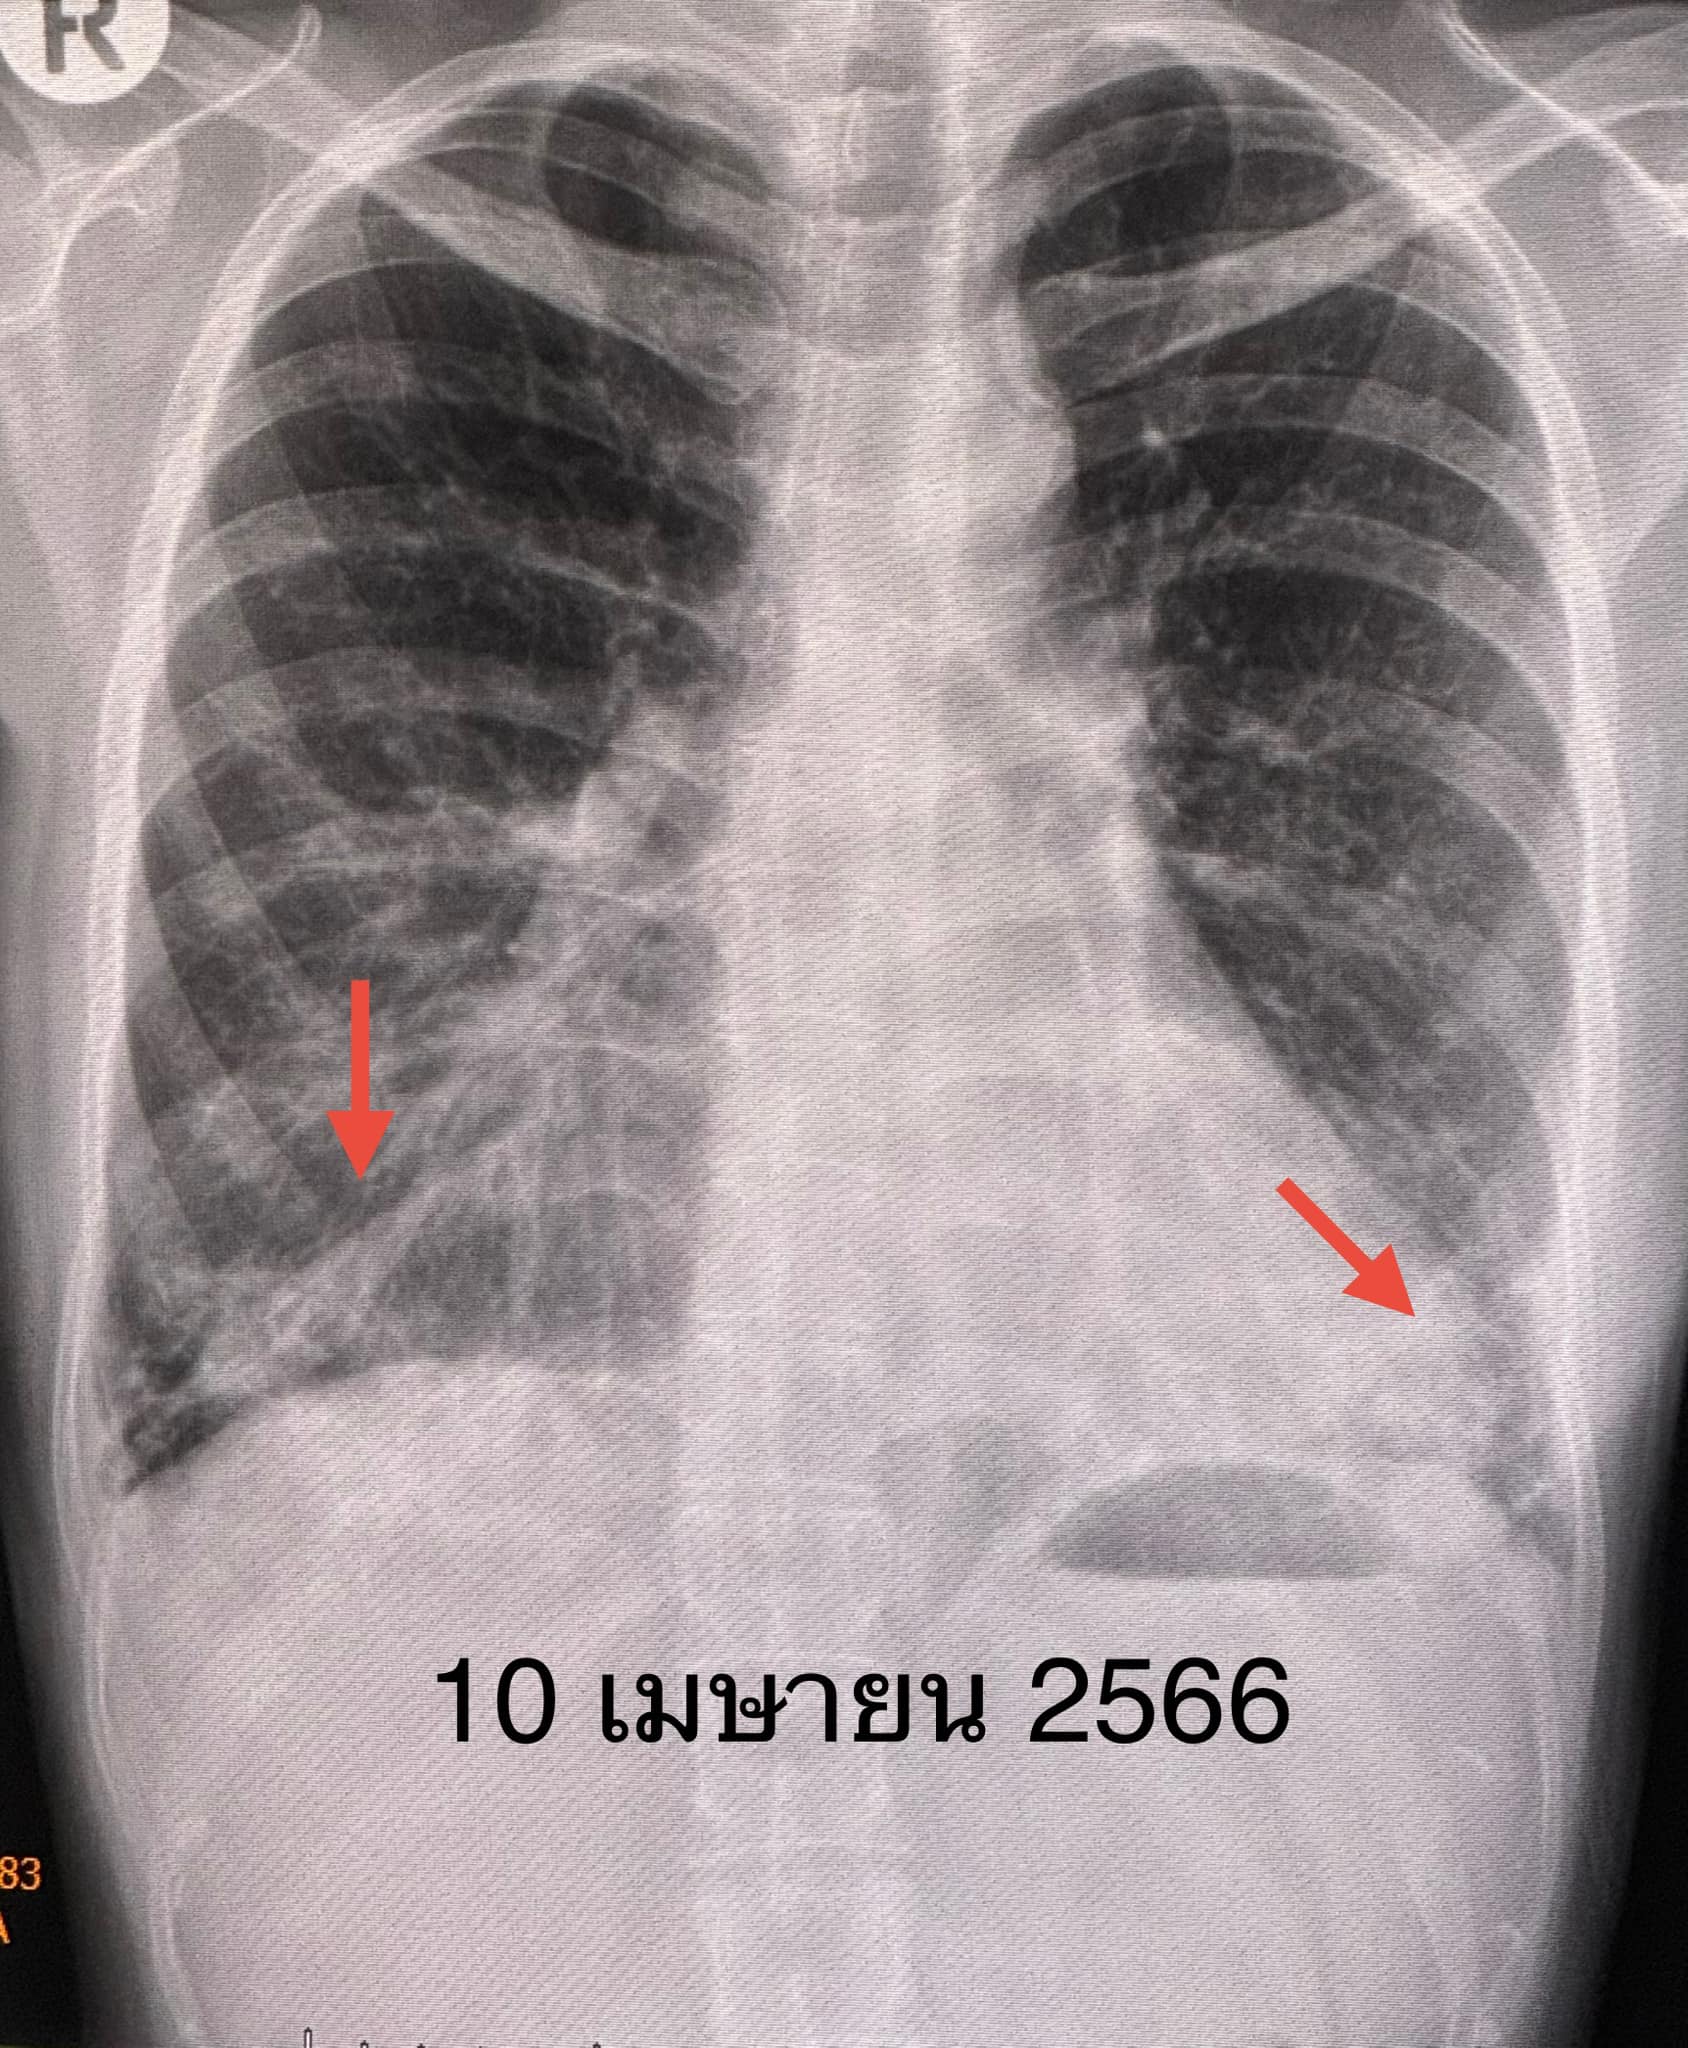

ผู้ป่วยได้วัคซีนไฟเซอร์เข็มที่ 3 เดือน ม.ค. 2566 เพราะกลัวว่าหากติดไวรัสโควิด-19 อาจป่วยรุนแรง เนื่องจากกำลังกินยากดภูมิคุ้มกัน ปรากฏว่า 5 วันหลังฉีดวัคซีนไฟเซอร์ ผื่นที่หน้า ข้อมือ ข้อศอก คอ หลังส่วนบน กลับมาเป็นมากขึ้น ไอ เหนื่อยเวลาออกกำลังกาย เอกซเรย์ปอดและคอมพิวเตอร์ปอดเห็นฝ้าขาวเพิ่มขึ้นที่ปอดด้านล่างทั้ง 2 ข้าง(ดูรูป)

วินิจฉัย: โรคภูมิต้านตนเองผิวหนังและกล้ามเนื้ออักเสบกำเริบหลังฉีดวัคซีนไฟเซอร์เข็มที่ 3 ต้องปรับเพิ่มขนาดยาสเตียรอยด์ และไมโคฟีโนเลต เพิ่มยาไฮดรอกซีคลอโรควิน (hydroxychloroquine) หลังปรับยา อาการดีขึ้นช้าๆ ผิวหนังดีขึ้น ไม่เหนื่อย